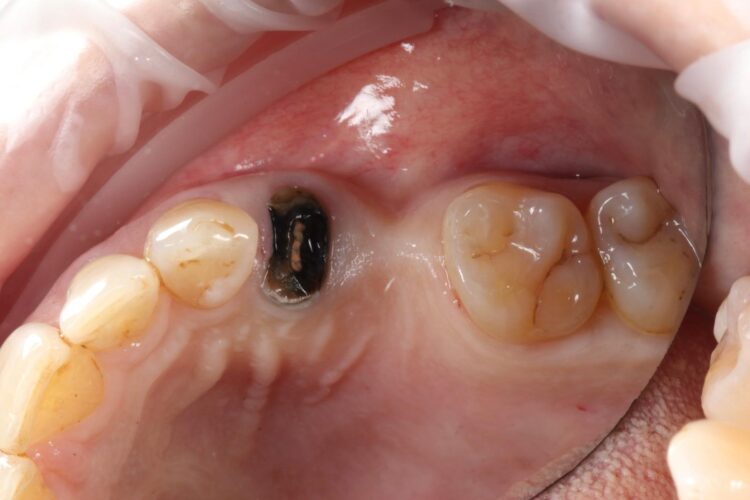

A 58-year-old female patient presented looking to improve the aesthetics and function of her dentition. During a consultation with another clinician, she had been offered conventional implant treatment involving the removal of the UL4 – which had root-filled a retained root – and delayed implant placement. The patient was hesitant to proceed in this way due to the predicted treatment time and expense.

Upon presentation, the initial assessment suggested that an immediate implant may be viable for the UL4 site, alongside simultaneous implant placement in the already healed UL5 site.

A comprehensive clinical assessment was conducted. The patient was generally fit and healthy, was taking no medication, had no allergies and maintained fair oral hygiene. The UL5 site, which had been edentulous for approximately seven years, presented with a substantial depression. This made immediate and simultaneous implant placement even more appropriate for the UL4/5, utilising the bone peaks around the UL4 to create a more favourable UL5 implant position and simultaneous augmentation. Other findings of note were signs of tooth wear on the UL3 and UL6, although these were periodontally sound and completely stable.